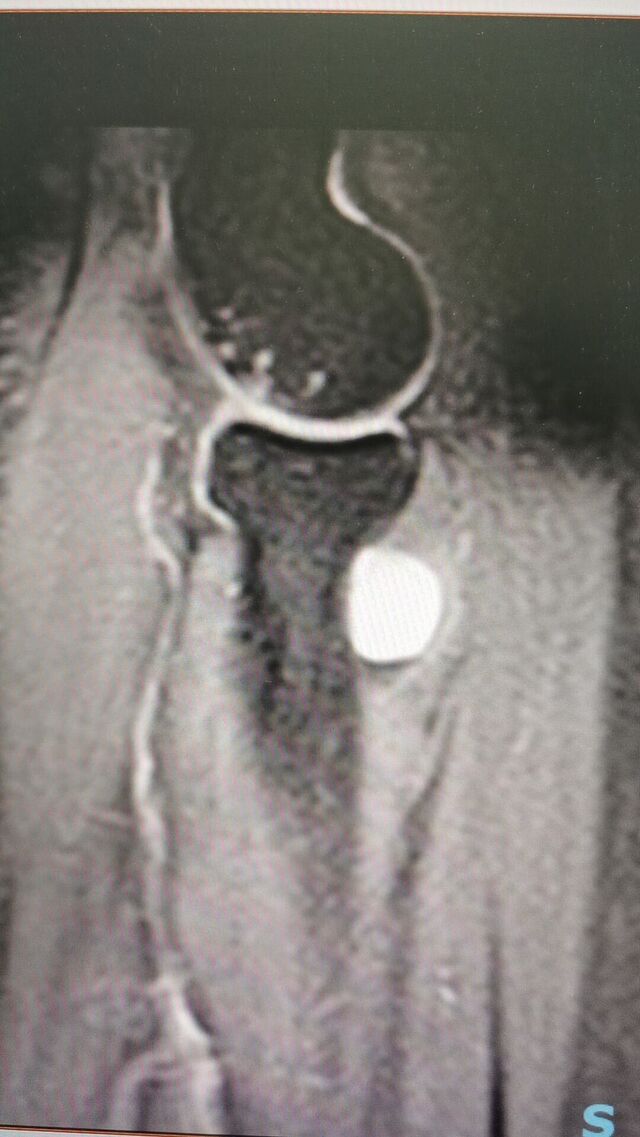

复习断层解剖: